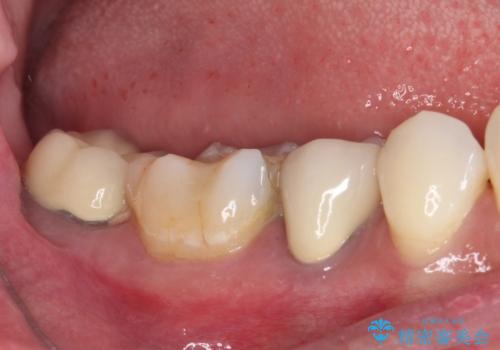

- ヨーロッパ駐在期間中に治療を受けた歯がしみるとのことで来院された患者様です。

ドイツやベルギーなどで治療を受けた奥歯2本が食事の度にしみているとのことで、レントゲン検査や視診を行ったところ、補綴物や修復物の適合が悪く、それが原因であると考えられました。

いずれの歯も症状に異常なく、オールセラミッククラウンにて補綴治療を行うこととしました。